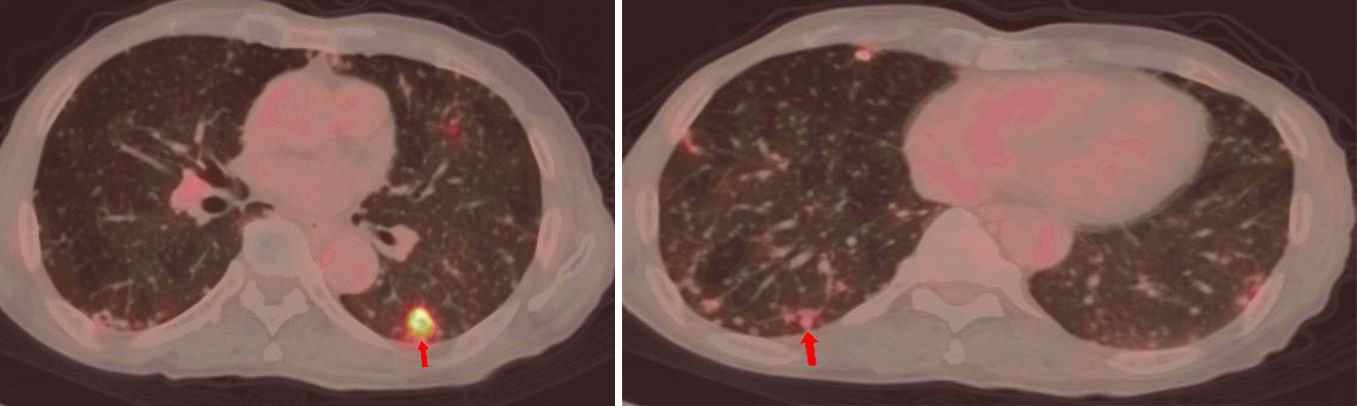

雙肺彌漫分布大小不等轉(zhuǎn)移灶